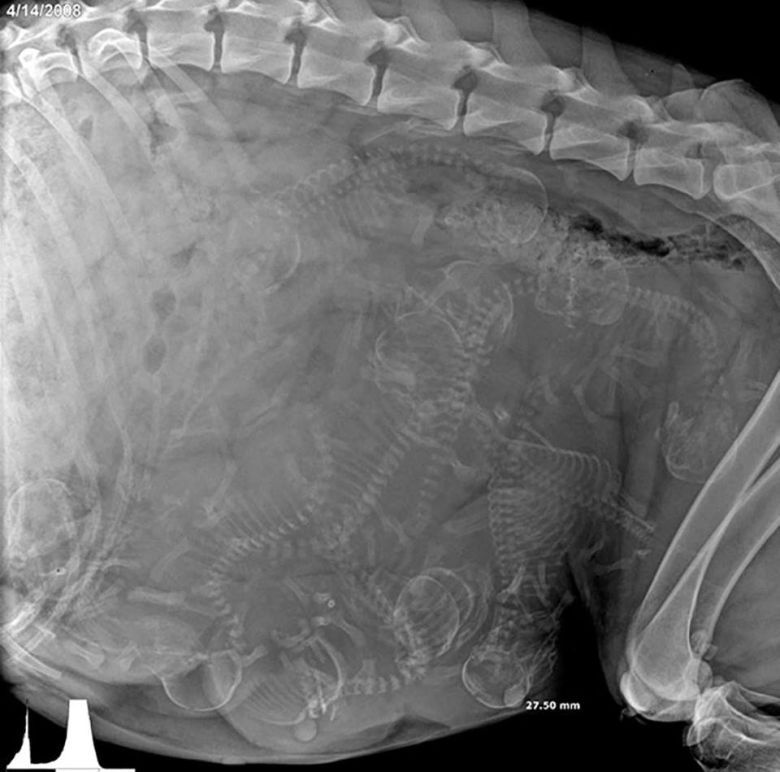

Zdjęcia rentgenowskie psa w ciąży